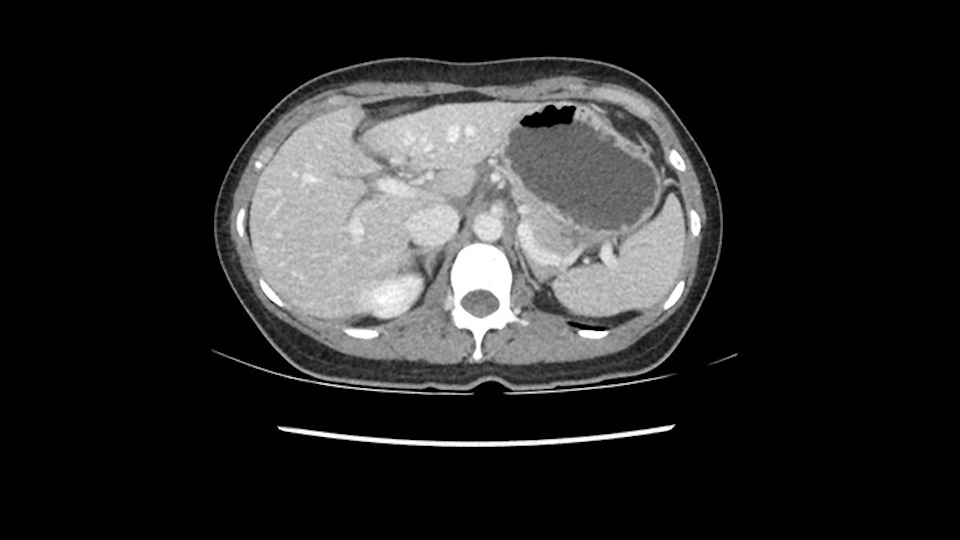

So if we look at the CT scan, on the axial, it’s a larger lesion. It’s about 6 or 7 or 8 centimeters. So it does look a bit threatening in terms of its resectability but if you really drill down deeply into the anatomy, and I think the coronal [imaging] is even better, you can see that the entire mass is on the patient’s left side of the falciform ligament. So it’s really only a left-sided tumor and not even really a left-sided tumor because Segment 4 is uninvolved anatomically.

None of the parenchyma is affected and this tumor is very exophytic; like many Hepatitis B hepatomas; and otherwise is resectable with either a wedge resection part of Segment 2-3 or a formal left lateral segmentectomy.

As I review the CT scan, we have both arterial and venous phases, the tumor is obvious. But I’ll start by saying that the liver itself does not appear to be cirrhotic to my eye. It’s got a normal contour and allied to that, that I do not see evidence of portal hypertension. The spleen is normal, there’s no collateral vessels. The tumor itself, I measured maximally at about 11 centimetres in diameter and I’m told the alpha fetoprotein is very high (over 10000), which is entirely consistent with this being a solitary hepatocellular carcinoma that is very exophytic. It seems to emanate off the inferior margin of Segment 3 (because that’s the falciform). I’ll start by saying that this is not transplantable. The tumor exceeds our guidelines for transplantation, but it's likely resectable based on normal liver and no portal hypertension.